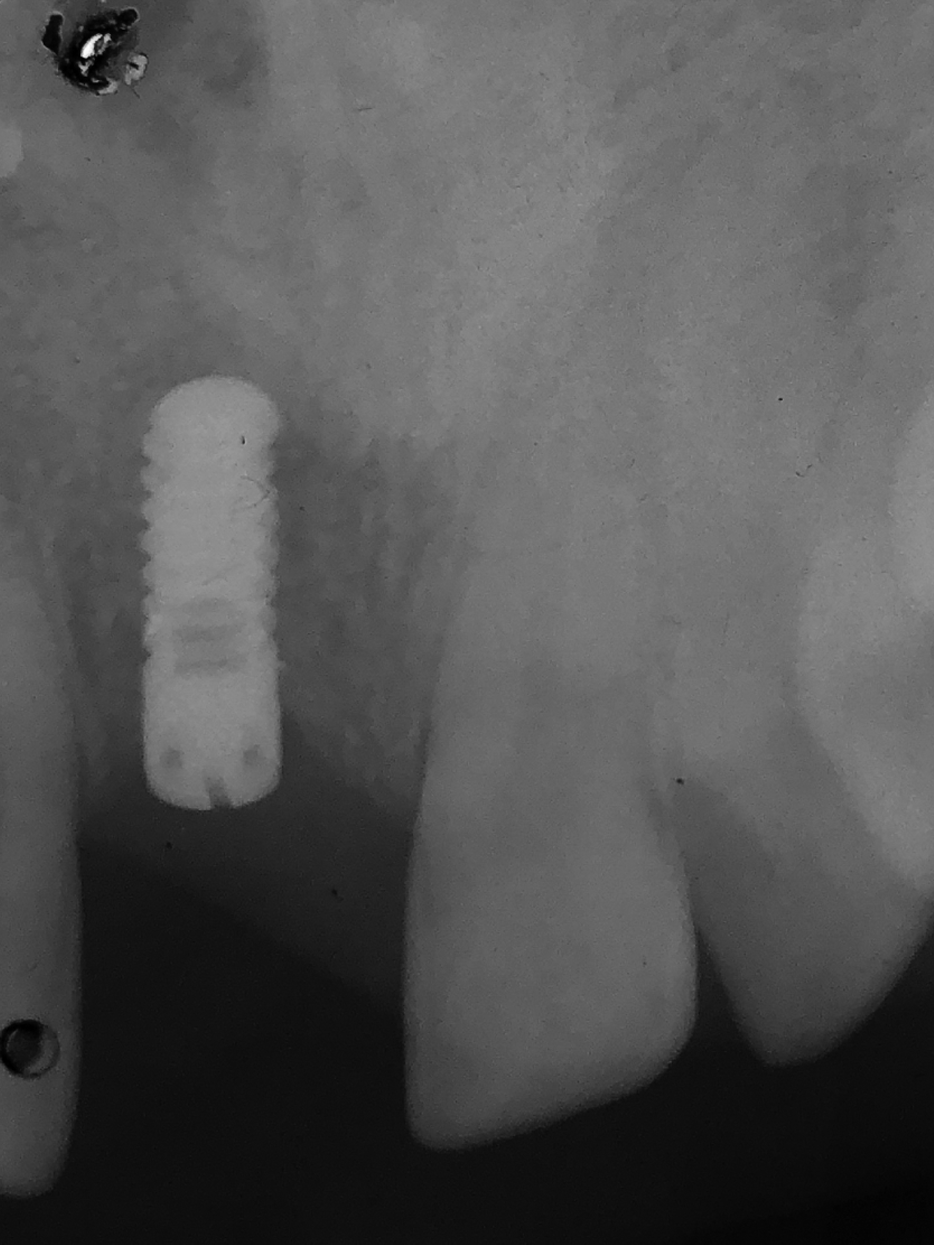

Nach der Einheilung wurde im Juni 2002 eine metallkeramische Krone zementiert. Bei regelmäßigen Recalls wurden weder objektive noch subjektive Änderungen erkannt. Die Kontrollaufnahme vom Januar 2003.